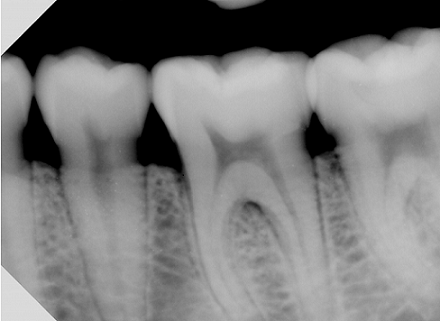

X光检测

X射线的波长比可见光短且具备穿透性,当被拍摄物体,如人体的组织或其他被检测物体有着密度和厚度的差异,经X射线透射后,被吸收的程度不同,经过X光探测器成像后即可得到不同的影像。

南北微自有的X光无损检测专利,支持在像素级高效自动检测X光,并使探测器从低能耗状态下唤醒并快速成像,可以有效避免多次曝光反复拍摄。